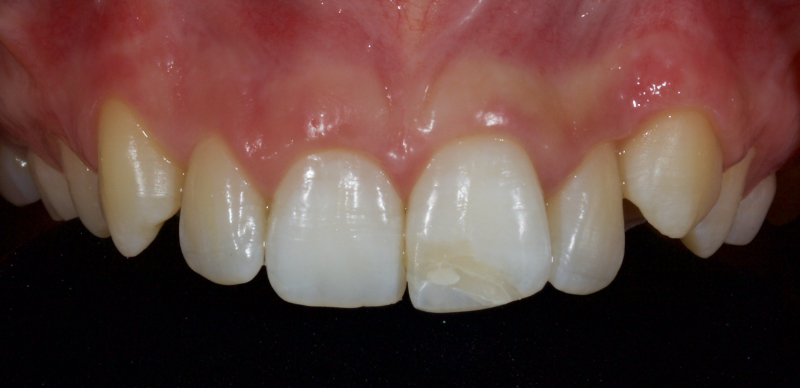

This article explores a more modern, minimally invasive approach to discolored non-vital teeth using the “modified walking bleach” approach. Figure 3 (before treatment) and Figure 4 (after treatment) show an example of this highly conservative approach.

In this example of the Modified Walking Bleach Approach, the patient presented with a discolored upper right central incisor (1.1, Fig. 7). The old restoration was removed, an endodontic retreatment was carried out, and a coronal barrier seal was placed (Fig. 8). The access cavity was left open (Fig. 9).